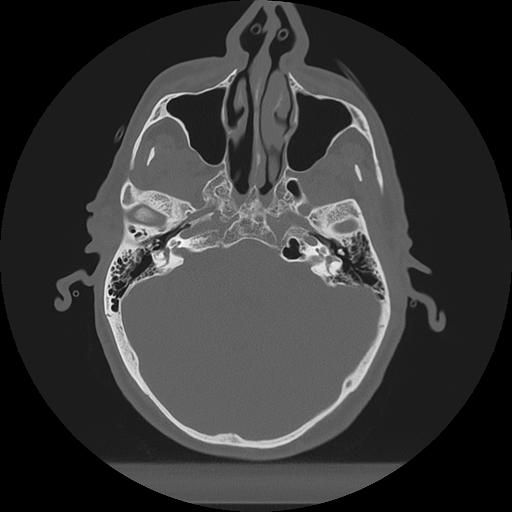

11 HUESO,,Axial,2.0,HUESO,,